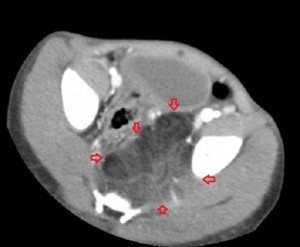

All the images in the lower panel are MR images (from left to right, axial unenhanced T1; fat-suppressed T1 post-gadolinium; coronal T1 without fat suppression; fat-suppressed sagittal T2). They show the extent of the disease better than CT and confirm that it is primarily lipomatous with little soft-tissue content. It infiltrates most of the left gluteal muscles, occupies the entire left perineum and ischiorectal fossa, and extends proximally in the retroperitoneum to the level of the sacral promontory.